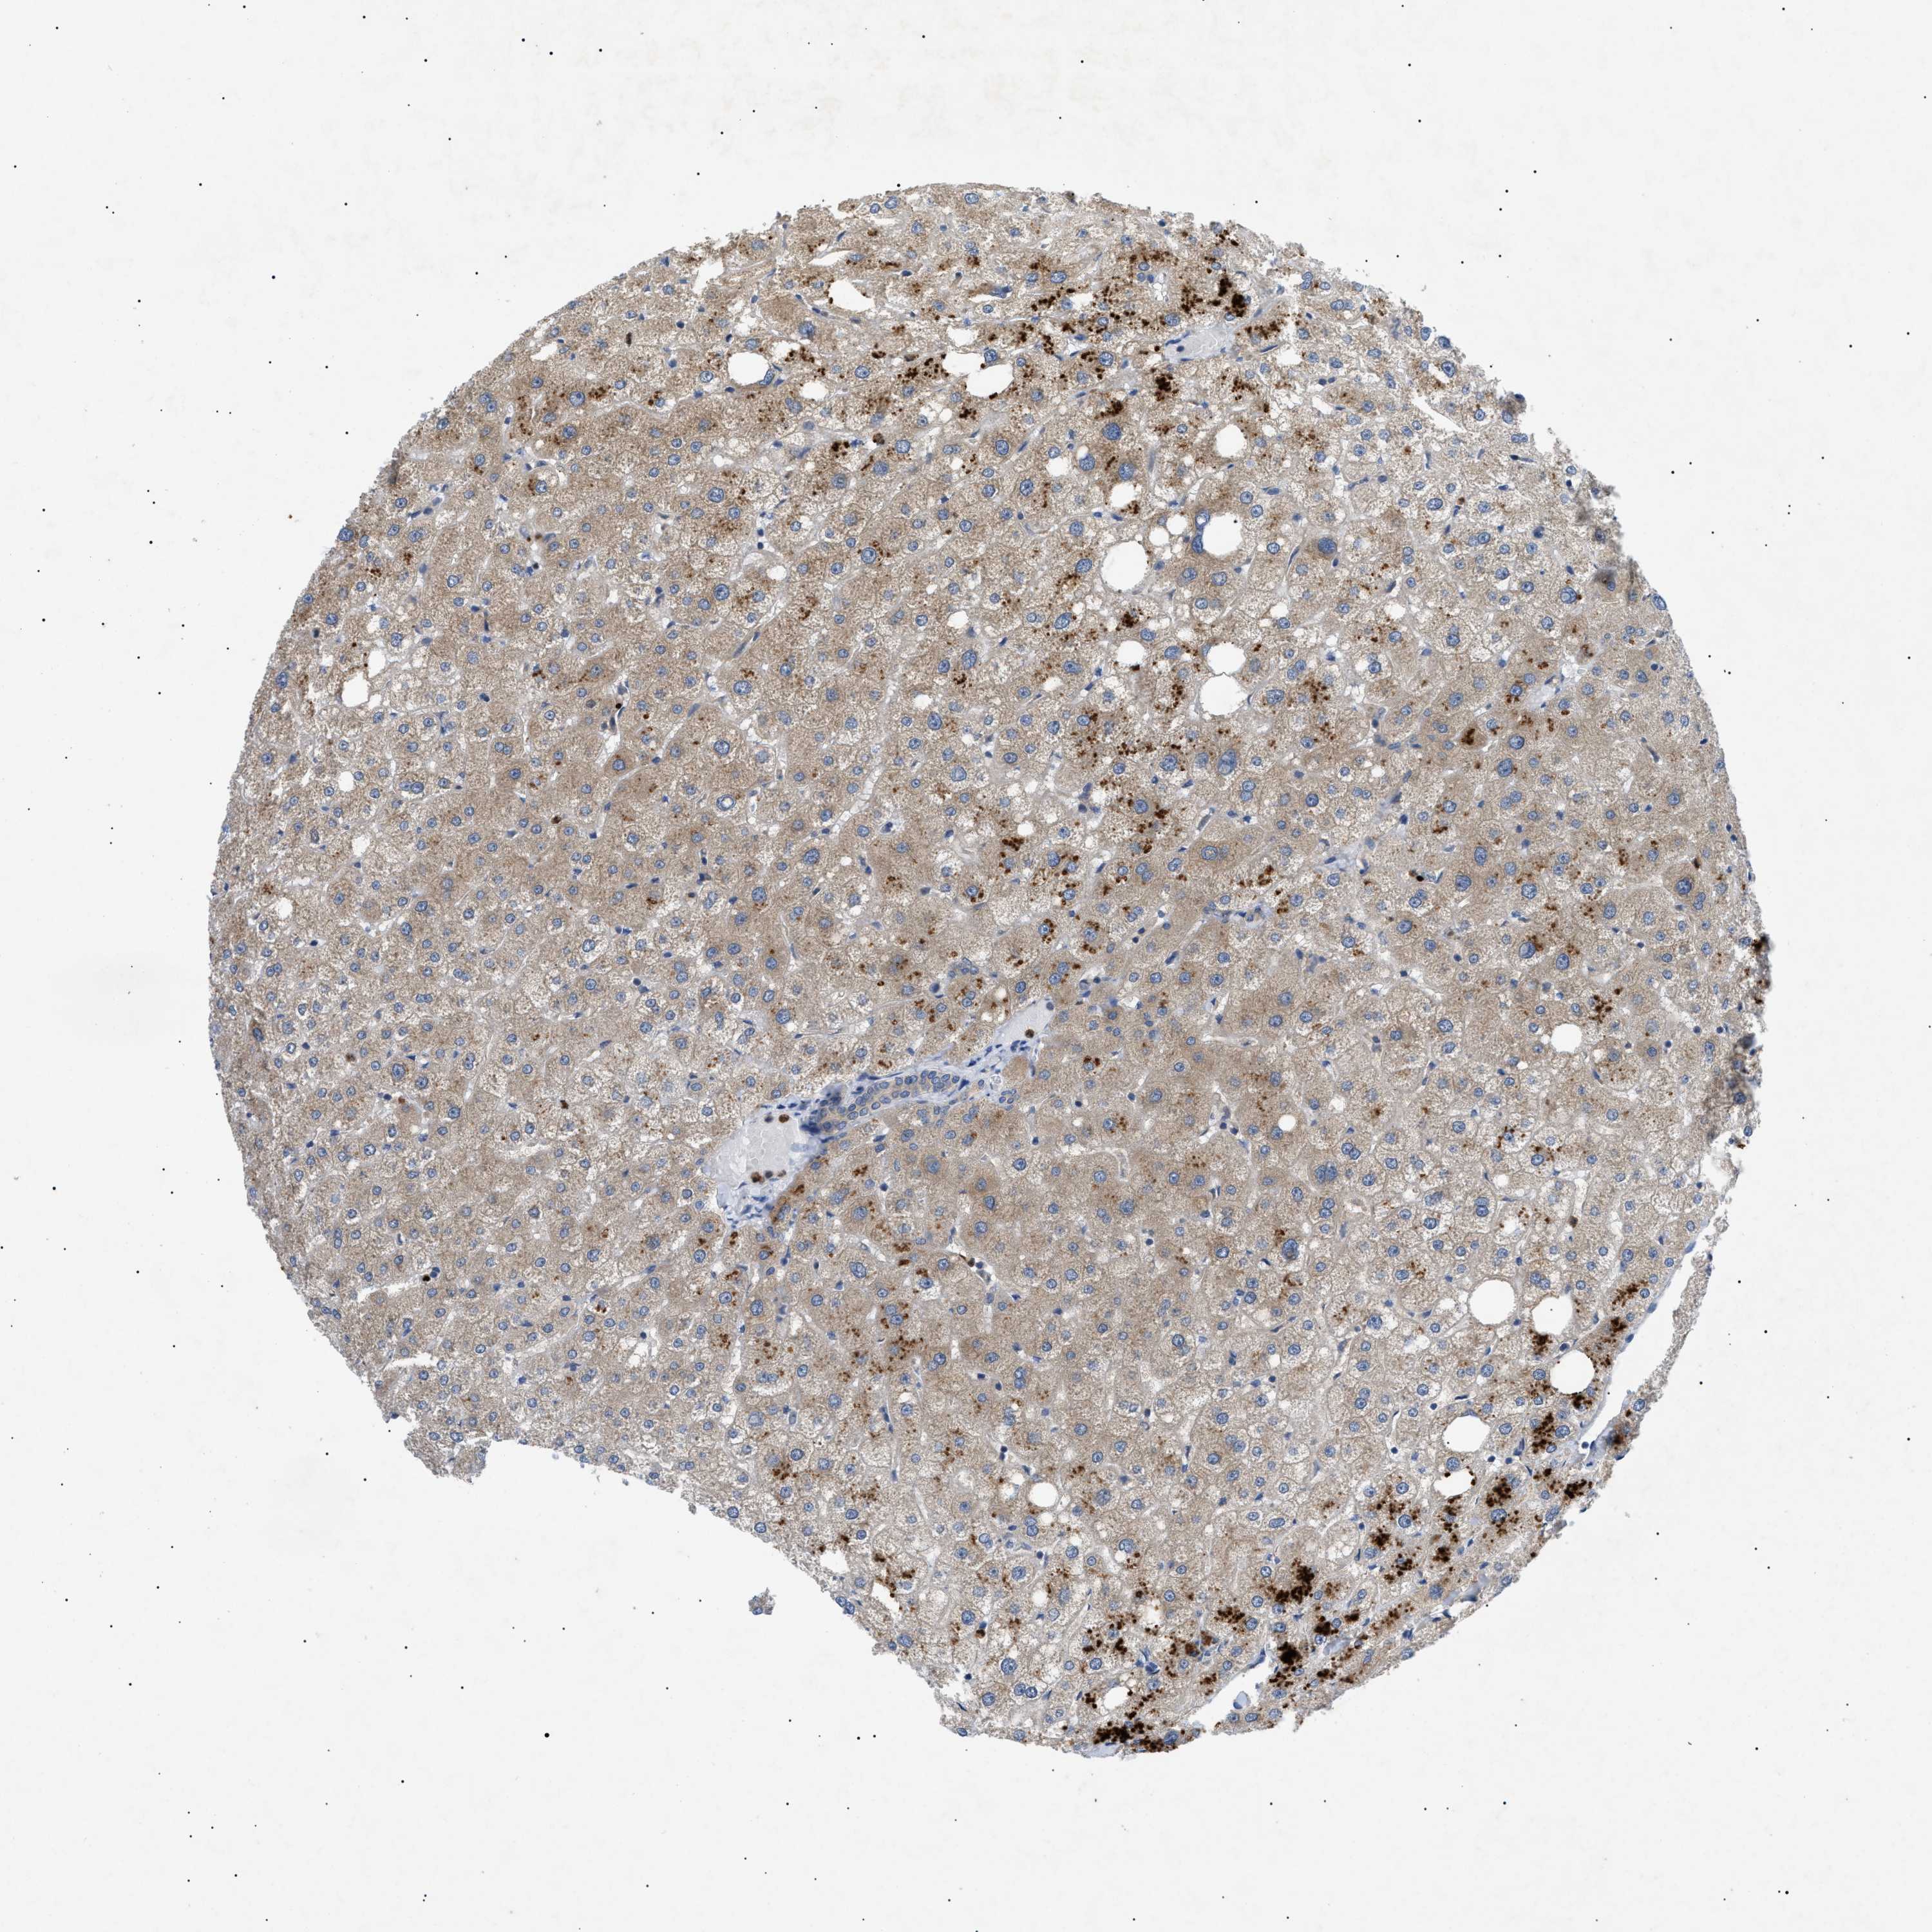

LIVER - Antibody stainingi

Antibody staining in the annotated cell types in the current human tissue is reported as not detected, low, medium, or high, based on conventional immunohistochemistry profiling in selected tissues. This score is based on the combination of the staining intensity and fraction of stained cells.

Each image is clickable and will lead to virtual microscopy that enables deeper exploration of all samples and also displays staining intensity scores, fraction scores and subcellular localization as well as patient and tissue information for each sample.

Antibody HPA015257Antibody CAB010302

Cholangiocytes Not detectedMedium

Hepatocytes LowMedium